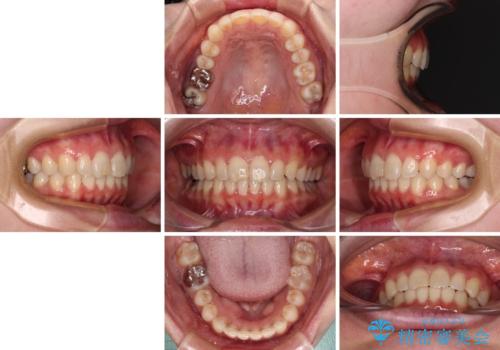

上下ともにデコボコの程度は著しいものではなく、インビザラインで十分に対応可能な歯列不正でした。

後戻りによりスペースができてしまうことを避ける目的で、IPR(歯と歯の間を削る)を極力用いない矯正治療を行うこととしました。

- 11ヶ月